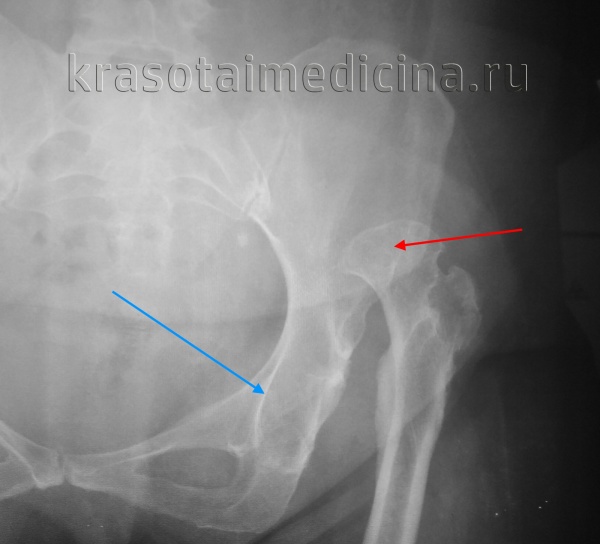

На рентгенограмме правого тазобедренного сустава видно: врожденный вывих бедра, ремоделированная и уплощенная головка бедренной кости (красная стрелка), недоразвинутая вертлужная впадина (синяя стрелка).